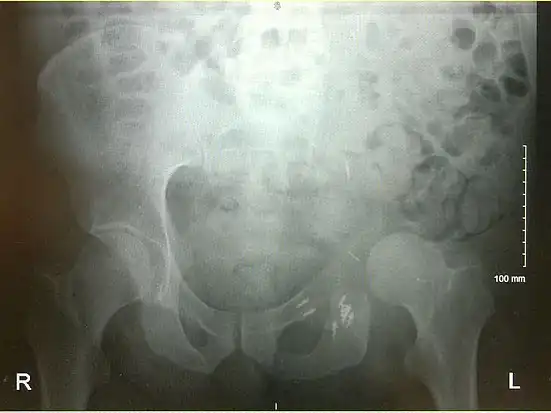

An x-ray of a limb-sparing hemipelvectomy on the left side of a male pelvis taken one month after surgery.